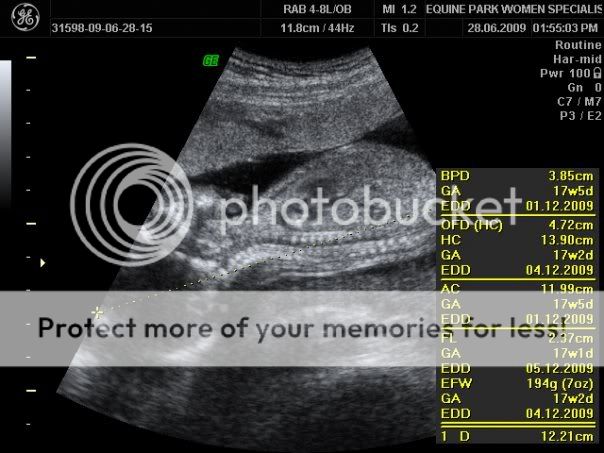

28.06.09

今天再次去Dr. Leong那儿产检,医生没有帮我验血,因为政府诊所有拿我的血,下一次产检时,只要把政府诊所的验血报告,医生会帮我详细解说。

这次医生检查的非常仔细,开始是量宝宝的头部,再来是身体,手和脚。

从数据中看到,宝宝成长的很健康,重量是194公克,羊水也足够

医生告诉我,暂时还不会感到胎动,因为看到里面还有空间让宝宝翻来覆去,可能再多2-3星期才会有胎动的现象。

医生也检查乐宝宝的眼睛,鼻子,耳朵,最重要的嘴唇,因为要看有没有兔唇。

在下来就看心脏,医生定格让我看宝宝的心脏有4个心房,证明健康。

同时,看到肋骨和脊椎骨。Dr. Leong说多数宝宝的肋骨都没问题的。

医生也慢慢找了左手,右手,左脚和右脚。

最后当然是看看我的小牛牛是牛仔还是牛妞

找啊找啊,看到尖尖的部分 ------- 医生说我的小牛牛应该是牛仔

下个月产检时,应该就可以更肯定了